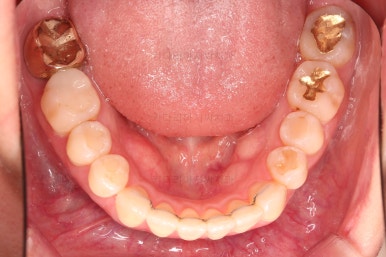

1. 초진

부산개방교합 키다리아저씨치과에 처음 내원 시 입안의 모습입니다.

전반적으로 치열이 삐뚤고요.

앞니쪽이 다물어지지 않는 개방교합(오픈바이트, open bite) 을 보였습니다.

어금니 맞물림을 보면 앵글씨 2급 부정교합 양상이어서 위아랫니가 모두 1대1로 부딪히고 있는 상태였습니다.